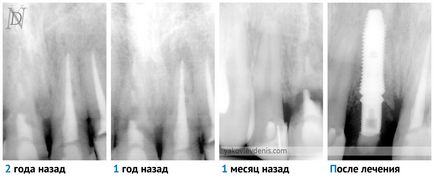

Klasszikus technológia beültetés azt sugallja, hogy a fogászati implantátumok kell tenni néhány hónap után annak eltávolítását. Ebben az esetben, ha szükséges, további műveletet végrehajtottuk kapacitása a csontszövet és az implantátum folyamat és a protézis (koronák beállítás) is el van egymástól időben. Miután az implantátum behelyezése, mivel néhány hónappal a osseointegration az implantátum ágyazott csont. Helyett hosszú távú hiánya a fogak, annak a ténynek köszönhető, hogy az állkapocs csont nem tapasztal rágás terhelés, általában egy csontreszorpciót. Ezért gyakran szükséges elvégezni csontpótlás.

Ha az implantátum azonnal foghúzás után az ilyen problémák nem merülnek fel, mert a csont nem elsorvadt.

5. A telepítés után a fogászati implantátumok az állkapocs csontreszorpciós folyamatban a csont felfüggesztett vagy megszűnik teljesen. Foglalkoztat a törvény Wolf - terhelt csont nem sorvadás (nem szívódik fel).